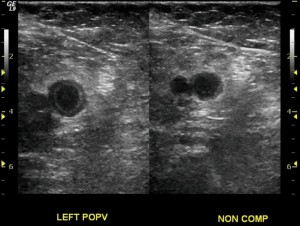

The diagnosis of DVT with duplex ultrasound relies on a combination of three ultrasonographic signs: 1) Direct visualization of the clot, 2) Non-compressibility of the area of the vein where there is clot in the lumen (as seen in the image above in the popliteal vein) and 3) Absence of augmentation when there is clot distal to the area being imaged. These methods may be complemented by color flow duplex that may aid in showing color defects that correspond to clots.